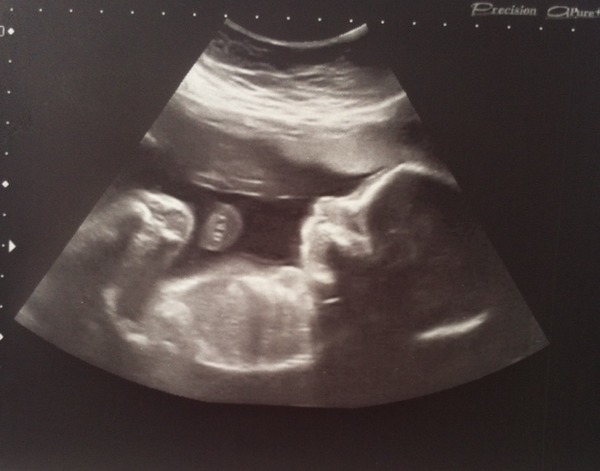

Now I've worked out how to post pics from my mobile (I know, I blame the baby) here's one of my 20 week scan: